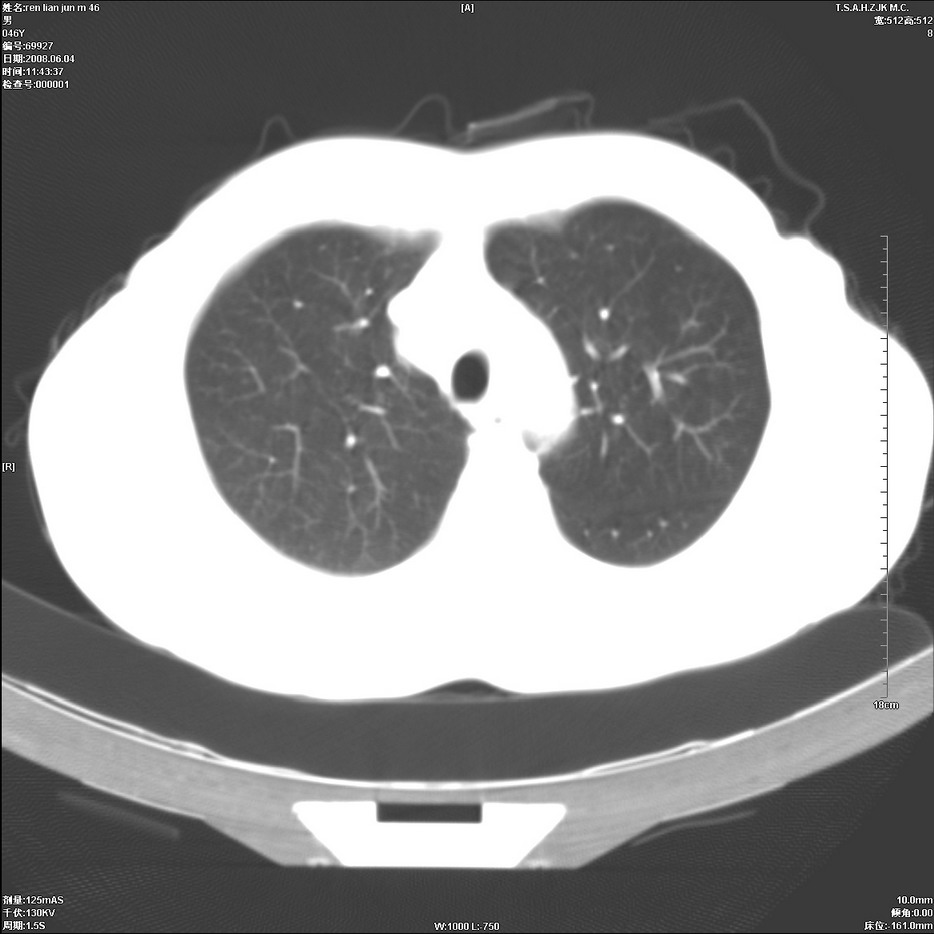

以下是引用qiu999在2008-6-5 17:14:00的发言:[br]考虑右肺中心型肺癌.颅内应做增强检查.

以下是引用形影不离在2008-6-5 19:18:00的发言:[br]右肺中心型肺癌并纵隔及左侧腋窝淋巴结转移,颅内应做增强检查。

以下是引用杀毒软件在2008-6-5 18:33:00的发言:[br]支持考虑右肺中心型肺癌,颅内病变是不是转移,不好说